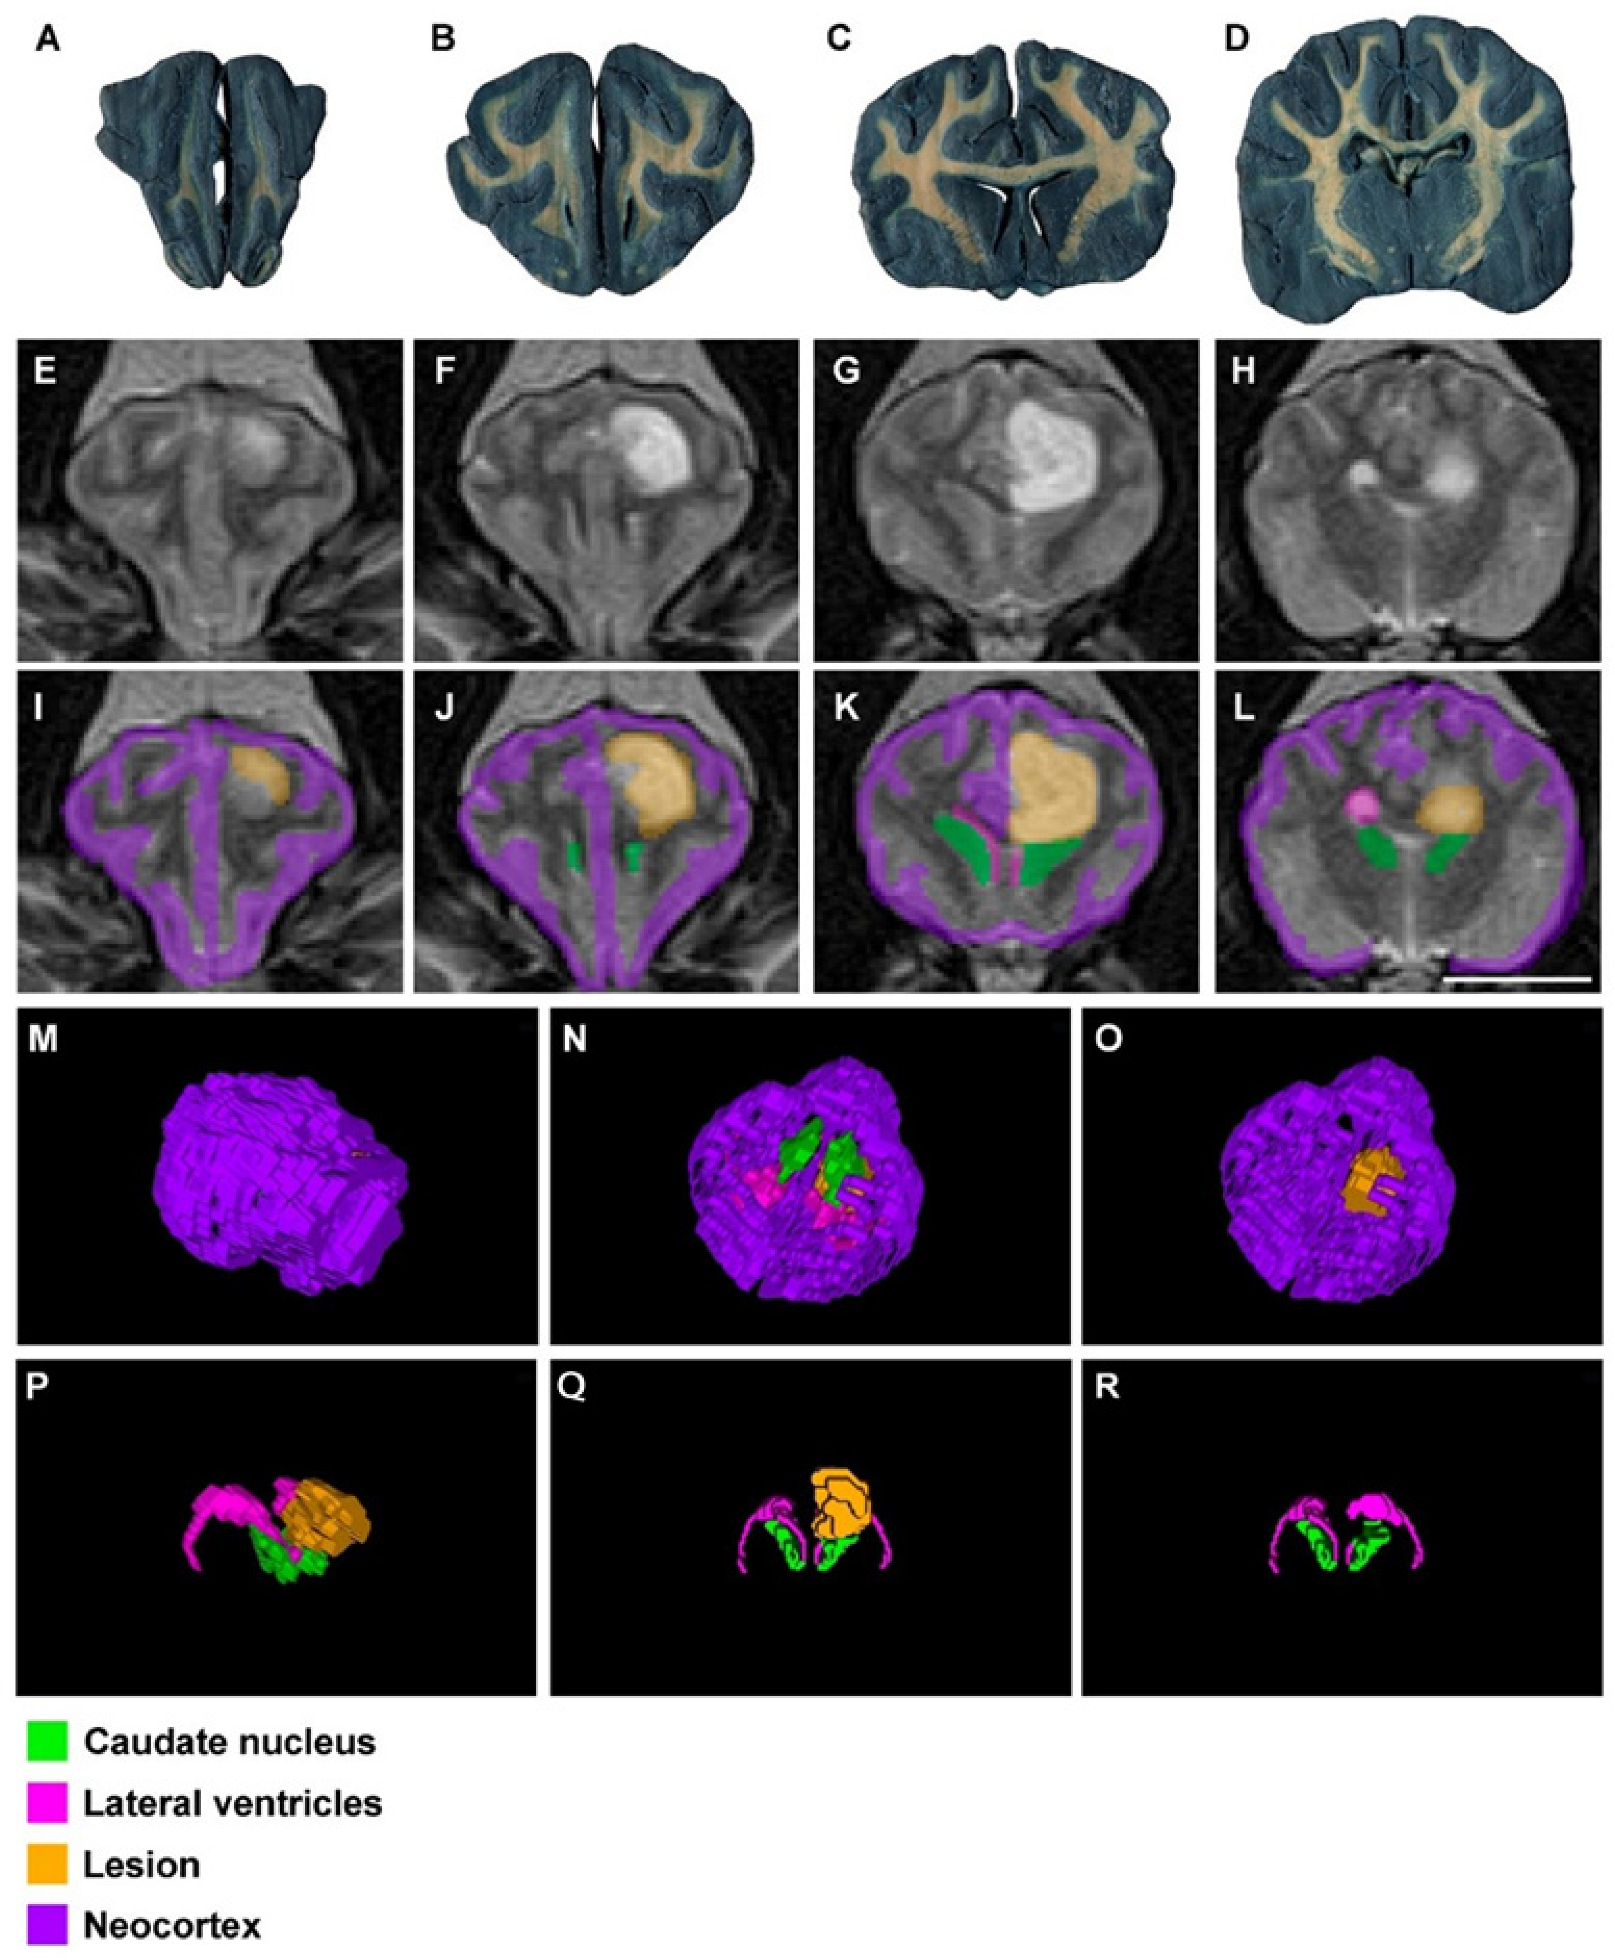

3. Results